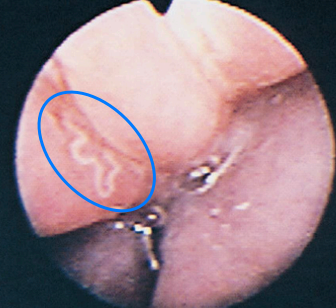

Nasal Capillariasis

Capillaria boehmi

- nematode

- 성체는 작고, 하얗고, thin

- nasal cavity와 frontal sinus의 mucosa에 서식

- 증상 : 재채기, 농성 콧물 (w or w/o hemorrhage)

- 진단 : 분변 검사(fecal flotation) - double operculated Capillaria egg를 확인

또는 rhinoscopy로 육안 확인 - 치료 : 진단은 어렵지만 약물로 금방 치료 가능